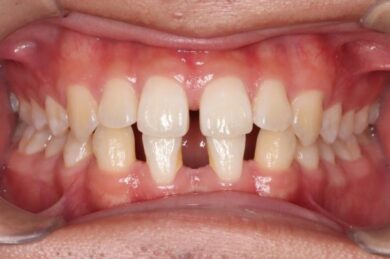

下顎の前歯は通常6本ですが、中央から2番目の歯(側切歯)が左右2本とも欠損している先天性欠如の患者様です。

初診時、下顎だけでなく、上顎の正中(真ん中)にも空隙(隙間)がありました。

• 治療前